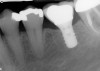

Figure 11  The mandibular first molar was fractured. Note the periapical lesions around this tooth.

Figure 11

Figure 12  After the first molar was extracted and hemisected without damaging the interradicular bone, an initial osteotomy was prepared in the interradicular bone utilizing a 2.2-mm-wide bur.

Figure 12

Figure 13  A radiograph of a guide pin in the prepared osteotomy.

Figure 13

Figure 14  An implant with a 4.8-mm-wide body and a 6.5-mm-wide restorative platform was placed in the interradicular bone following appropriate preparation.

Figure 14

Figure 15  Another view of the implant in the interradicular bone. Note that the mesial and distal aspects of the interradicular septum have been lost. The implant attained primary stability from the buccal and lingual aspects of the interradicular bone.

Figure 15

Figure 16  A radiograph of the restored implant taken after more than 7 years in function demonstrates stable peri-implant crestal bone levels.

Figure 16